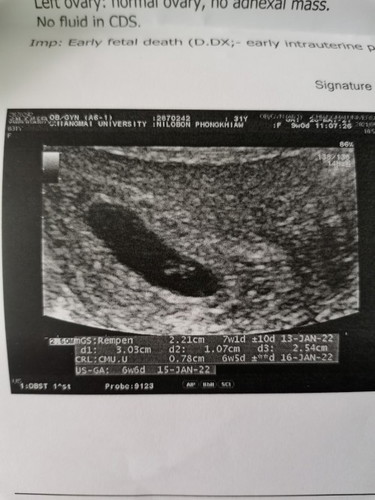

#ขอคำแนะนำหน่อยค่ะ เราหาหมอครั้งแรก 4w ซาวด์ทางช่องคลอดไม่เจออะไร หมอนัดต่อ 6w ซาวด์ทางช่องคลอด เจอถุงตั้งครรภ์และจุด หมอว่าเป็นถุงไข่แดง หมอนัดต่ออีก 8w ครั้งนี้ซาวด์ผ่านหน้าท้อง เจอถุงตั้งครรภ์ที่ใหญ่ขึ้น แต่ตัวอ่อนวัดได้แค่ 0.78cm. หมอว่ามีขนาดเท่ากับ 6w และไม่เจอหัวใจ หมอว่าน้องอาจเสียในครรภ์ไปแล้วค่ะ ให้ยุติการตั้งครรภ์ เราควรรอต่อไปมั้ยคะ เผื่อว่าจะเจอหัวใจน้อง หรือเชื่อหมอและยุติคะ?